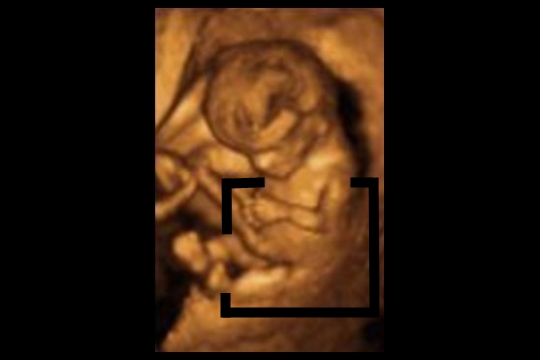

Corte coronal